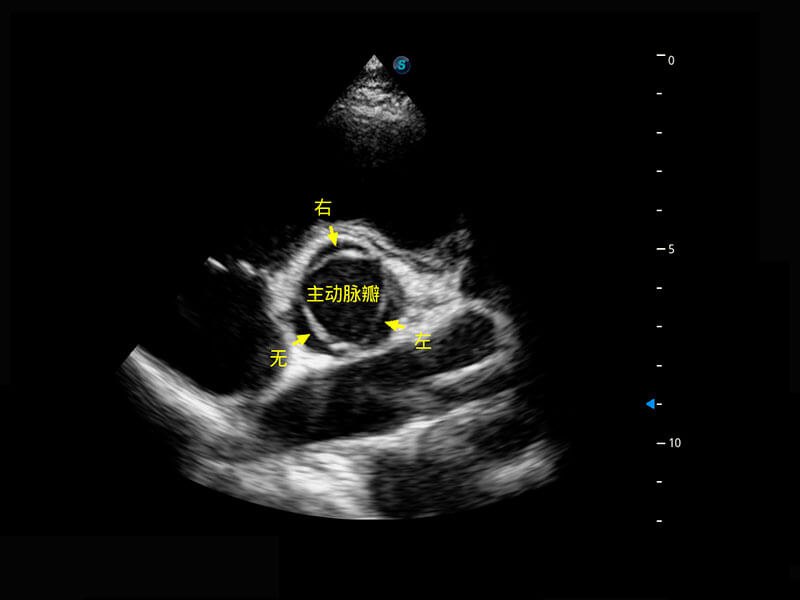

胎心筛查

P60搭载一系列胎儿心脏成像技术,实现精细的胎儿心脏评估。

• 右室双出口

• 胎心容积成像